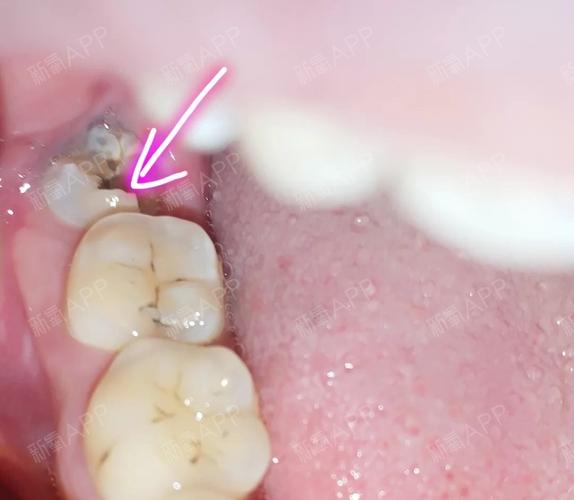

蛀牙初期 症状:牙齿上有小黑线和小黑点,牙斑 做法:初期是预防的zui

龋齿初期图片

龋齿初期图片,龋齿的发展过程图片

龋齿初期